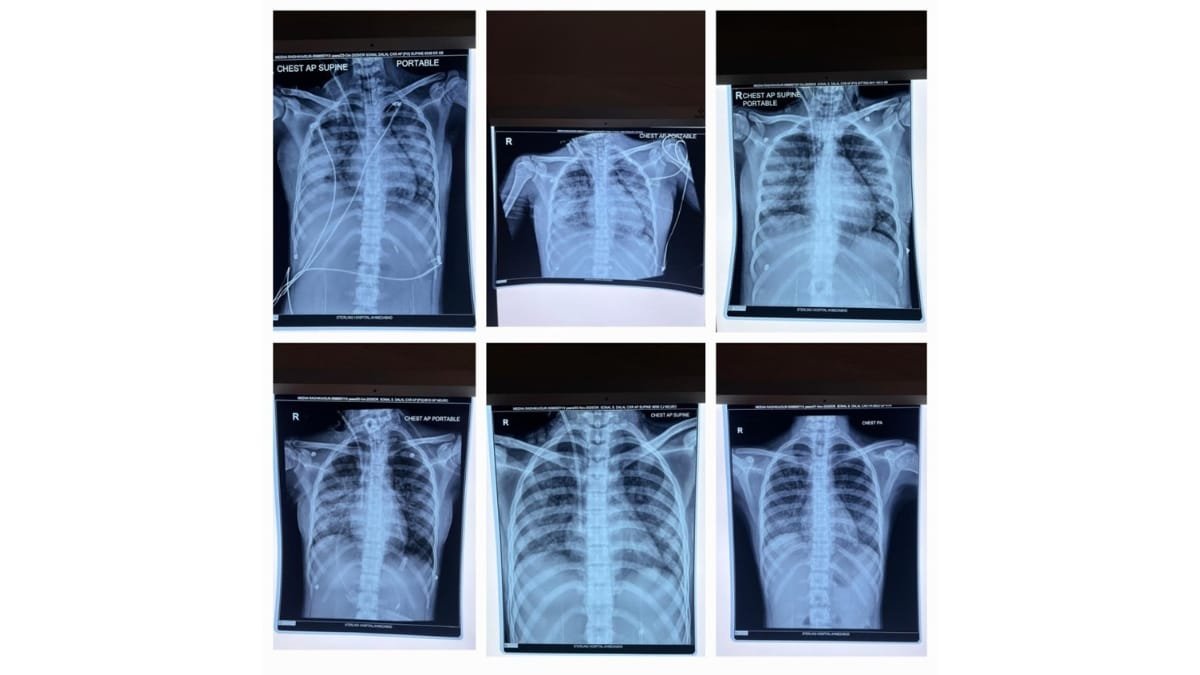

Ahmedabad (Gujarat) [India], December 10: In an inspiring example of medical excellence, doctors at Sterling Hospital, Gurukul, Ahmedabad, have saved the life of a 15-year-old girl who was battling severe Plasmodium falciparum malaria and multiple organ failure. The teenager was rushed from Rajasthan to Sterling Hospital in an extremely critical condition, struggling to breathe and dependent on ventilator support. She was diagnosed with falciparum malaria that had caused acute kidney injury, lung damage, and multi-organ complications. Under the expert care of Dr Sonal Dalal and Dr Amrish Patel (Pulmonologist & Critical Care Specialist), the ICU team initiated rapid, advanced treatment, including dialysis and specialised critical care support. She remained on a ventilator for 12 days and showed steady improvement with round-the-clock monitoring.

Sterling Hospital, Ahmedabad’s Dr Amrish Patel (Pulmonologist & Critical Care Specialist) explained that when the patient arrived, her oxygen levels were dangerously low, and she was struggling to breathe. She had been shifted from Rajasthan on ventilator support due to her fragile condition. The team immediately initiated specialised treatment to stabilise her. She was diagnosed with falciparum malaria, which had led to kidney damage, lung complications, and multi-organ involvement. After dialysis and medical management, she remained on ventilator support for 12 days, during which her life was saved through advanced care administered by the critical care team.

Dr. Amrish Patel (Pulmonologist & Critical Care Specialist) added that a bronchoscopy was performed to clear the secretions from her lungs. An essential step that further contributed to her recovery. As her condition improved, the ventilator support was gradually removed, and she was shifted to a normal room. By then, she had entered the recovery phase. After approximately 18 days of treatment, her life was saved through advanced care, and she was discharged in a stable and healthy condition.